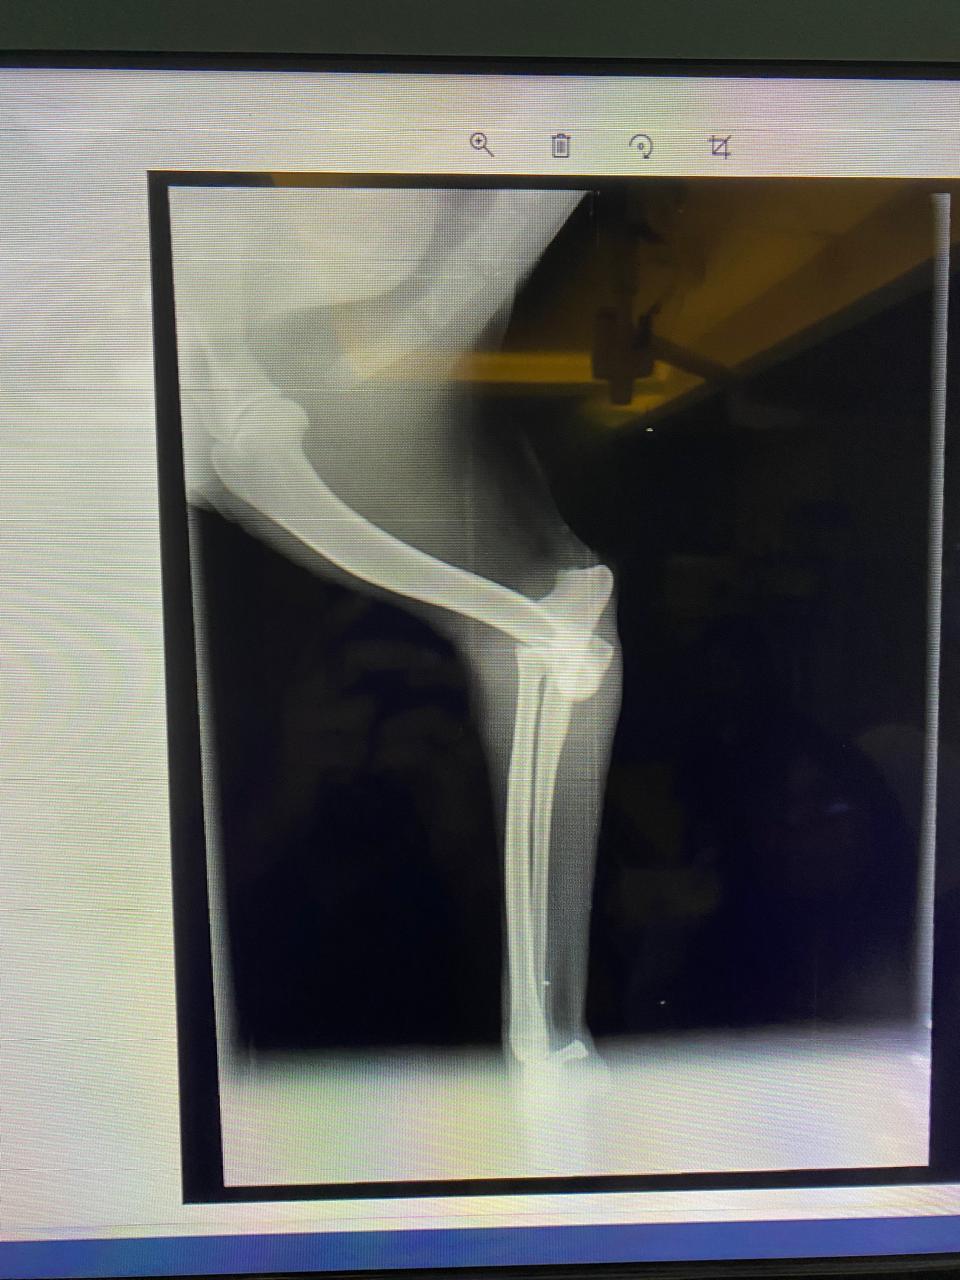

Manche Geschichten lassen einen sprachlos zurück – Dropies ist eine davon. Gefunden haben wir sie bei einer unserer Kastrationsaktionen. Eigentlich wollten wir ihre Mutter mitnehmen, doch die Anwohner wehrten sich vehement – Kastration sei „haram“. Innerhalb von Sekunden wurde die Hündin verjagt. Und dann sahen wir Dropie: ein kleines humpelndes Hundekind, mitten unter ihren sechs Geschwistern. Der nächste Streit begann – diesmal um Dropie selbst. Wir wussten: wir können sie nicht zurücklassen. Zum Glück konnten wir uns durchsetzen und Dropie mitnehmen. Ihr Hinterbein war schwer verletzt – laut Anwohnern wurde sie von einem Auto überfahren. Doch niemand half ihr. Sie lag tagelang einfach dort, in ihrem Schmerz. In der Top Vet´s Tierklinik offenbarte das Röntgenbild das ganze Ausmaß: ein alter, komplizierter Bruch. Doctor Essam war ehrlich – eine Operation wäre schwierig. Aber wir wollten ihr Beinchen nicht einfach aufgeben. Leider blieb der Erfolg aus – die OP brachte nicht die erhofften Besserung. Doch Dropie ist eine Kämpferin. Sie nutzt ihr Bein, bewegt sich, spielt – und scheint, soweit die Ärzte es beurteilen können, schmerzfrei zu sein und nur das ist es was zählt. Eine Amputation ist weiterhin ein Thema, aber nur, wenn es medizinisch notwendig wird. Solange sie noch im Wachstum ist, beobachten wir die Entwicklung ihres Beines.